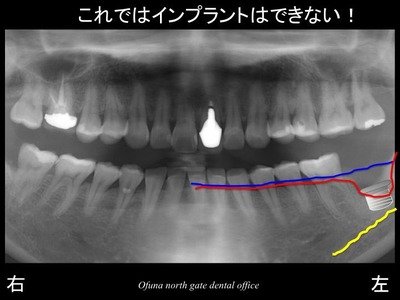

それでは、いつものように 骨吸収の状態を分かりやすくするために

骨吸収の状態を線で書いたのが以下のレントゲンになります。

青線が骨吸収を起こす前の骨の位置です。

赤線は、現在の骨の位置です。

かなりの骨吸収が起こっているのが分かるかと思います。

現状ではインプラントを埋め込むことはできません。

また、骨吸収以外にもインプラントを埋め込むことを困難にさせていることがありました。

それは、下顎神経の存在です。

骨吸収と下顎神経の存在から

インプラント治療が難しい状態になっていました。